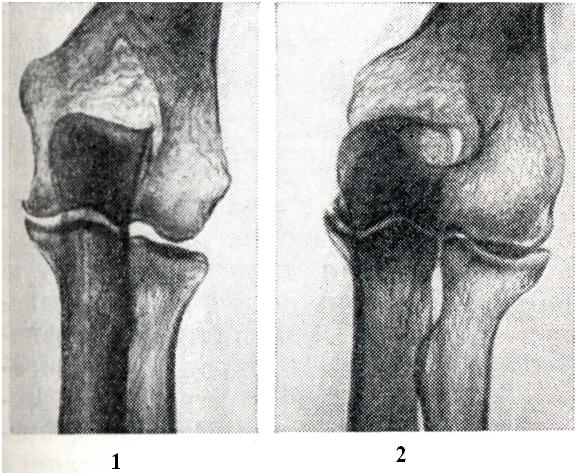

При старении хряща в нем доминирует анаэробный гликолиз, в результате чего увеличивается содержание лактата и уменьшается рН. Это увеличивает активность указанных ферментов, так как оптимальное их действие бывает в кислой среде, и деградация компонентов межклеточного вещества хряща еще больше усугубляется. В ответ на увеличенную деполимеризацию протеино-полисахаридных комплексов и уменьшение компонентов хряща наступает пролиферация хондроцитов и усиление синтеза хондроитинсульфата. Таким образом, дистрофия хряща постепенно про¬грессирует, поверхностный слой его приобретает клочковидную структуру. Кроме того, при А. изменяются свойства синовиальной жидкости, к-рая является хорошим смазочным средством, особенно за счет гиалуроновой кислоты. Это тоже способствует развитию артроза. Синовиальная оболочка, богатая соединительнотканными элементами, кровеносными и лимфатическими, сосудами, нервами, тоже принимает участие в развитии артрозов, особенно при появлении реактивных воспалительных реакций. При электронномикроскопическом изучении синовиальной оболочки выделены два типа клеток: тип А и тип В. Клетки типа А являются преимущественно абсорбтивными и имеют способность фагоцитировать, а клетки типа В в основном вырабатывают комплексы гиалуроновой кислоты и протеинов. При артрозах активность этих клеток вначале усиливается, а по мере прогрессирования процесса ослабевает. Причины, вызывающие пуск этого механизма, неизвестны. Полагают, что может иметь значение генетическая предрасположенность, обусловленная дефектом в синтезе полисахаридов и ферментов хряща. В этиологии и патогенезе вторичных артрозов главную роль играют травмы, нарушающие целость или конгруэнтность (соответствие) суставных поверхностей. Другими причинами вторичных артрозов являются врожденные дисплазии и приобретенные нарушения статики, перенесенные артриты, заболевания эпифизов костей, заболевания обмена веществ (например, подагра, охроноз, болезнь Кашина — Бека), эндокринные заболевания (гипотиреоз, сахарный диабет и другое). Врожденные и приобретенные дефекты хряща и других элементов костно-суставного аппарата в сочетании с продолжающейся или даже увеличивающейся нагрузкой на суставы могут через определенный период времени привести к развитию артрозов. Учитывая то обстоятельство, что травмы и микротравматизация, аномалии статики (варусное или вальгусное положение бедер, голеней и стоп, плоскостопие, врожденный вывих или дисплазия бедра, кифоз, лордоз, сколиоз и другое), перенесенные болезни костей (асептические некрозы) и суставов (артриты) и некоторые другие состояния весьма часто являются причиной развития артроза, Хаккенброх (М. Hackenbroch, 1968) предложил называть их преартрозами и принимать профилактические меры для предупреждения артроза. В основе патологоанатомических изменений при артрозе лежат прогрессирующие дистрофические и некробиотические процессы в суставном хряще, сопровождающиеся деформацией сочленовных поверхностей костей (рис. 1). Отсюда наиболее распространенный термин — деформирующий артроз. Как правило, в процесс вовлекаются эпифизы костей, что дает основание называть заболевание также остеоартрозом. Деформирующий артроз чаще всего развивается в суставах конечностей. Однако могут поражаться и межпозвонковые диски (смотри Дискартроз). Макроскопическая картина деформирующего артроза зависит от стадии заболевания. В ранней стадии отмечается разволокнение, шероховатость, прежде всего по краям суставного хряща. В дальнейшем наблюдается его истончение, узурирование и образование бугров различных размеров. В далеко зашедших случаях по краям хрящевого покрытия образуются костные разрастания — остеофиты. В участках, воспринимающих давление, поверхность, лишенная хряща, под влиянием постоянного трения как бы отшлифовывается. Костные «шлифы» имеют вид желобообразных вмятин. Все эти изменения обусловливают деформацию сустава. Головка бедра, например, может приобрести грибовидную, цилиндрическую форму или сплющиться. Деформируется также и суставная впадина (рис. 2). Значительные изменения претерпевают связки, синовиальная оболочка, капсула. Внутрисуставные связки становятся утолщенными, разрыхленными. При резком обезображивании сустава они могут подвергнуться некрозу, атрофии или срастись с суставной сумкой. Сосочки синовиальной оболочки увеличиваются в размерах, иногда приобретают древовидный характер. В строме их наблюдается развитие жировой ткани, хряща и кости. Такие сосочки могут отшнуроваться и превратиться в свободные внутрисуставные тела (смотри Суставная мышь). Количество синовиальной жидкости, как правило, резко уменьшено, что явилось поводом характеризовать заболевание как «сухое воспаление суставов». Микроскопическая картина деформирующего артроза складывается из дистрофических изменений суставного хряща (рис.3), сопровождающихся его васкуляризацией и оссификацией со стороны субхондральных отде лов кости. В краевых отделах может наблюдаться избыточная пролиферация хондробластов, которая не столько компенсирует убыль хрящевой ткани, сколько способствует обезображиванию сустава вследствие образования экхондрозов. Экхондрозы со временем подвергаются обызвествлению и замещению костной тканью с формированием столь типичных для артрозов остеофитов. В хряще определяется разволокнение, а также слизистая и жировая дистрофия основной субстанции, снижение содержания кислых мукополисахаридов. Эти изменения сопровождаются образованием многочисленных разрывов и щелей. Одновременно на границах с синовиальной оболочкой и костно-мозговыми пространствами отмечаются явления хондролиза и рассасывания хрящевой субстанции, в результате чего демаскируются проходящие здесь коллагеновые волокна. В поздних фазах возможен некроз хондроцитов и исчезновение волокнистых структур. Крупные очаги некроза хряща встречаются лишь в тяжелых случаях заболевания. В базальных отделах хряща появляются костномозговые полости, окруженные тонкими костными балками.

В субхондральных отделах отмечаются явления лакунарной резорбции и новообразования кости, а в зонах костных «шлифов» развивается остеосклероз. В более глубоких отделах эпифиза преобладает остеопороз с образованием кист, окруженных поясом склерозированной кости. Здесь же встречаются островки хрящевой ткани, которые, по мнению некоторых авторов, представляют собой разрастания хрящевой мозоли, распространяющейся из глубоких отделов необызвествленной зоны суставного хряща. В редких случаях островки хрящевой ткани в виде своеобразных «грыж» выбухают над поверхностью костных шлифов (рис. 4). Фиброзные и костные анктшозы при деформирующем артрозе, в отличие от артритов, не развиваются. Любой артроз развивается и протекает очень медленно и никогда не приводит к тяжелым нарушениям функции суставов и особенно к фиброзному и костному анкилозу. Исключением является тазо-бедренный сустав, отличающийся своими анатомическими особенностями (глубокая суставная яма, вмещающая около 2/3 головки бедренной кости, и сравнительно узкая суставная щель, быстро уменьшающаяся при любом патологическом процессе). В этом суставе очень рано наблюдается ограничение подвижности и вовлечение в процесс мышечно-связочных элементов, что в далеко зашедших случаях нередко является причиной инвалидизации больных. Однако анкилоз и в данном случае не наступает, если к артрозу не присоединяется воспалительный процесс. Любая форма артроза протекает без общих признаков воспаления (ускорение РОЭ, диспротеинемия, повышение температуры, исхудание и другого). Первичный артроз часто сопровождается нарушением жирового обмена, артериальной гипертензией, атеросклерозом и другими заболеваниями. Очень важной чертой артроза является несоответствие между морфологическими изменениями в суставах, наблюдаемыми на рентгенограммах, и клиническими проявлениями болезни. Иногда при незначительных рентгенологических изменениях отмечаются сильные боли и ограничение подвижности. В других случаях при значительных рентгенологических изменениях клинические симптомы оказываются весьма умеренными. Это зависит от нескольких причин. Во-первых, суставной хрящ полностью лишен сосудов и нервов. Поэтому его поражение не дает симптомов до тех пор, пока патологический процесс не выходит за пределы самого хряща. Во-вторых, синовиальная мембрана, суставная капсула, сухожилия и мышцы, имеющие многочисленные нервные рецепторы, воспринимающие боль, не во всех суставах поражаются в одно и то же время и в той же степени. В-третьих, не у всех больных артрозом развивается одинаково быстро: чем медленнее он начинается и протекает, тем менее выражены клинические симптомы, так как организм успевает использовать все компенсаторные приспособления. Суставные симптомы артроза складываются из болей, чувства скованности, быстрого утомления, тугоподвижности, деформаций, хруста и другого. Боли обычно тупые. Они непостоянны, усиливаются в холодную и сырую погоду, после длительной нагрузки (например, к вечеру) и при начальных движениях после состояния покоя («стартовые боли»). В тазо-бедренных суставах боли иррадиируют в паховую либо седалищную область (при этом отмечается напряжение отводящих мышц и сгибателей бедра). Очень часто, особенно при старческих артрозах, вместо болей отмечается лишь ломота и чувство тяжести в костях и суставах. Это ощущение весьма близко к чувству скованности при ревматоидном артрите, но отличается кратковременностью и малой интенсивностью. Истинное ограничение подвижности при артрозе наблюдается редко, чаще речь идет о тугоподвижности и быстрой утомляемости суставов. Все эти симптомы обусловлены нарушением конгруэнтности суставных поверхностей, изменениями (утолщением, кальцинозом, склерозом) в суставной капсуле, сухожилиях и других мягких тканях и спазмом мышц. Деформации суставов лучше всего заметны в дистальных межфалаиговых суставах рук (геберденовские узелки), в тазо-бедренном суставе (состояние флексии, аддукции и внешней ротации бедра), в коленных суставах (утолщение костной ткани за счет краевых остеофитов) и обусловлены костными разрастаниями, а ие набуханием мягких тканей, как при артритах. Причиной хруста суставов (чаще всего коленного) являются неровности суставных поверхностей, известковые отложения и склероз мягких тканей. В отличие от мелкого, крепитирующего хруста при синовитах, для артрозе характерен грубый хруст. Рентгенологическое исследование позволяет диагностировать артроз, установить стадию процесса, провести дифференциальную диагностику. Основным методом исследования при артрозе является рентгенография (смотри Артрография). Помимо стандартной рентгенографии, при наличии показаний применяют томографию, а также функциональную рентгенографию и рентгенокинематографию, которые позволяют определить амплитуду движений, взаимоотношения между суставными отделами костей при различных положениях сустава и так далее. При рентгенологическом исследовании выявляется, что поражение обычно начинается как моноартикулярный процесс, а при множественном поражении изменения в одном суставе превалируют над изменениями в других. Патологический процесс прогрессирует и постепенно становится полиартикулярным. Клинико-рентгенологически можно выделить три стадии в течении артроза. Первая стадия характеризуется незначительными изменениями. Происходит едва заметное сужение суставной щели, особенно в местах наибольшей функциональной нагрузки (например, в латеральном отделе щели тазо-бедренного сустава и в медиальном отделе щели коленного сустава), и появляются незначительные костные разрастания, преимущественно по краям впадины сустава (рис. 5). Вторая стадия отличается более выраженными изменениями (рис. 6). Сужение суставной щели становится хорошо видимым. Параллельно с изменениями суставной щели определяется перестройка суставных поверхностей. Поверхности эпифизов костей деформируются, уплощаются и становятся неровными; костные разрастания достигают значительных размеров и приводят к деформации суставных концов костей. Особенно резко это бывает выражено в тазо-бедренном суставе: головка бедра уплощается, значительно увеличивается в поперечнике и приобретает грибовидную форму. На характер деформации суставных концов костей влияет и статико-функциональная нагрузка на определенный сегмент конечности, в результате чего меняется конфигурация не только головки, но и впадины сустава (например, псевдопротрузия вертлужной впадины, уплощение суставной поверхности лопатки, болынеберцовой кости и так далее). Деформация суставных поверхностей сопровождается нарушением конгруэнтности, вплоть до развития подвывихов и вывихов в суставе. Нарушение взаимоотношений между суставными отделами костей влечет за собой перераспределение линий статико-функциональных нагрузок, что в свою очередь ведет к развитию деформации по типу coxa vara, humerus varus, дугообразному искривлению костей и так далее. В третьей стадии развития процесса наступают изменения в более глубоких участках костей, сопровождающиеся склерозом субхондральной костной ткани. Кроме того, выявляются различной величины очаги кистозной перестройки, которые при расположении в краевых субхондральных отделах костей образуют узуры, напоминающие туберкулезное поражение. Нередко во второй и особенно в третьей стадии артроза выявляются внутрисуставные тела, образующиеся в результате отрыва костных разрастаний и обызвествления некротизированного хряща (рис. 7). Внутрисуставные тела имеют неправильную форму, величина и количество их вариабельны. Истинная атрофия и регионарный остеопороз не характерны для артроза; исключение составляют артрозы, протекающие с резко выраженной болезненностью и нарушением функции сустава.